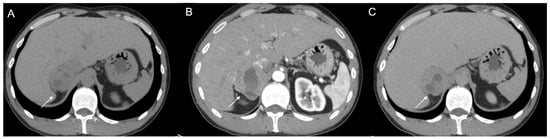

Figure 14.

Axial unenhanced (a), arterial (b), and coronal venous (c) CT phases show a lung carcinoid metastasis (arrow) of the left adrenal gland. Additional hypervascular metastasis can be seen in the liver, particularly in the arterial phase.